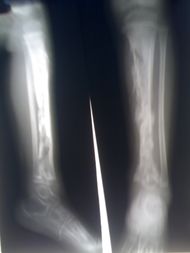

| Osteomyelitis of the tibia of a young child. Numerous abscesses in the bone show as radiolucency. | |

التهاب العظام Osteomyelitis مرض يصيب العظم ونِقْيَ العظم، (مادة هلامية في وسط العظام).